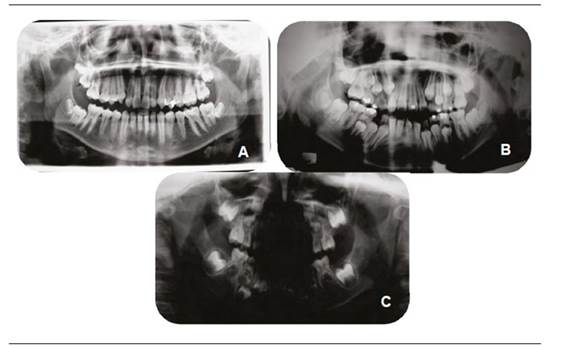

Si bien el diagnóstico es principalmente clínico, diversos exámenes complementarios permiten un mejor análisis de la patología. La ortopantomografía (Figura 2) permite un análisis inicial de las estructuras mandibulares y maxilofaciales, evaluando ambos lados en una misma imagen. Una telerradiografía de perfil permite evaluar, a través de la cefalometría, las relaciones entre maxilar y mandíbula, mientras que una telerradiografía frontal permite observar el grado de asimetría y desviación mandibular. Una radiografía oclusal otorga una visión apropiada de la bóveda palatina en caso de fisura labio-palatina.

En las imágenes se observan or topantomografías de pacientes con MHF, todas del lado derecho, pero con distintos grados de severidad (imagen A: Grado I; imagen B: Grado II e imagen C: Grado III). Se puede observar cómo, a medida que aumenta la severidad, la simetría entre las ramas y otras estructuras mandibulares se va reduciendo, y se pierde completamente la forma condilar en la imagen C.